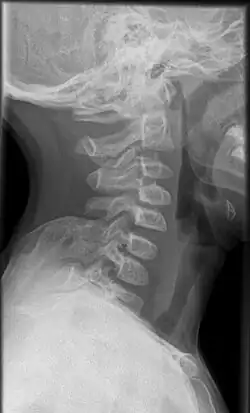

Häufig findet sich neben einer Verkürzung der Halsmuskulatur ein bindegewebiger oder knorpeliger Strang zwischen oberem Skapularand und Wirbelanhangsgebilden der unteren Halswirbelsäule. Ist dieser knöchern ausgeprägt, wird er als Omovertebralknochen, Os omo-vertebrale, bezeichnet und ist auf Röntgenaufnahmen erkennbar. In den anderen Fällen kann dieser Strang im Kernspintomogramm (MRT) dargestellt werden.

Os omo-vertebrale in Sprengel-Deformitaet, laterale Projektion HWS